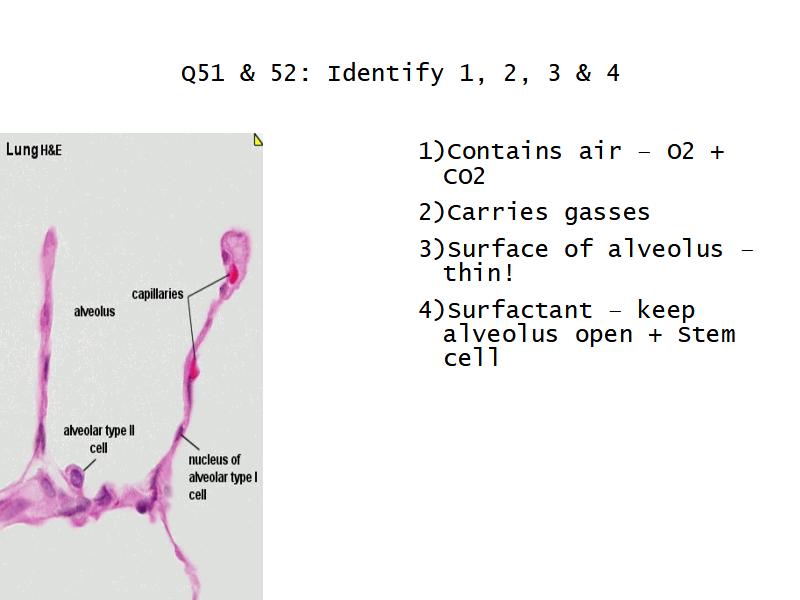

What cells are present?

Components of the Blood-Air Barrier?

- Alveoli